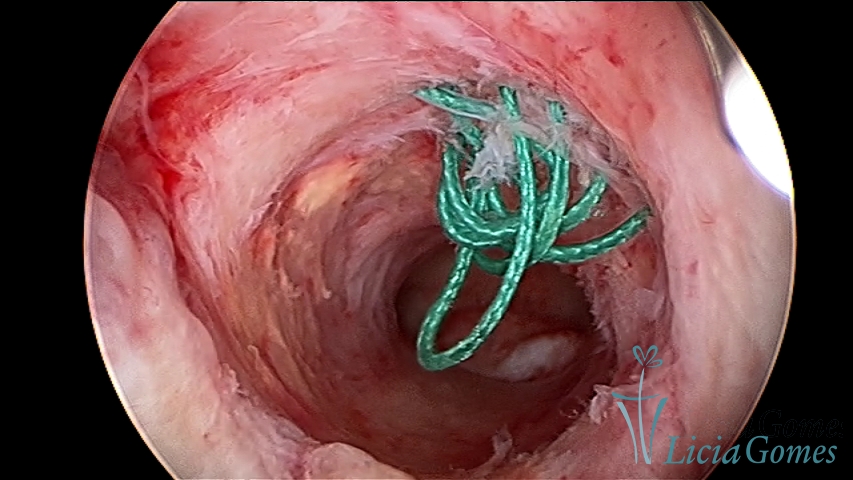

Panoramic view of a cesarean section scar with a non-absorbable suture for 30 years.